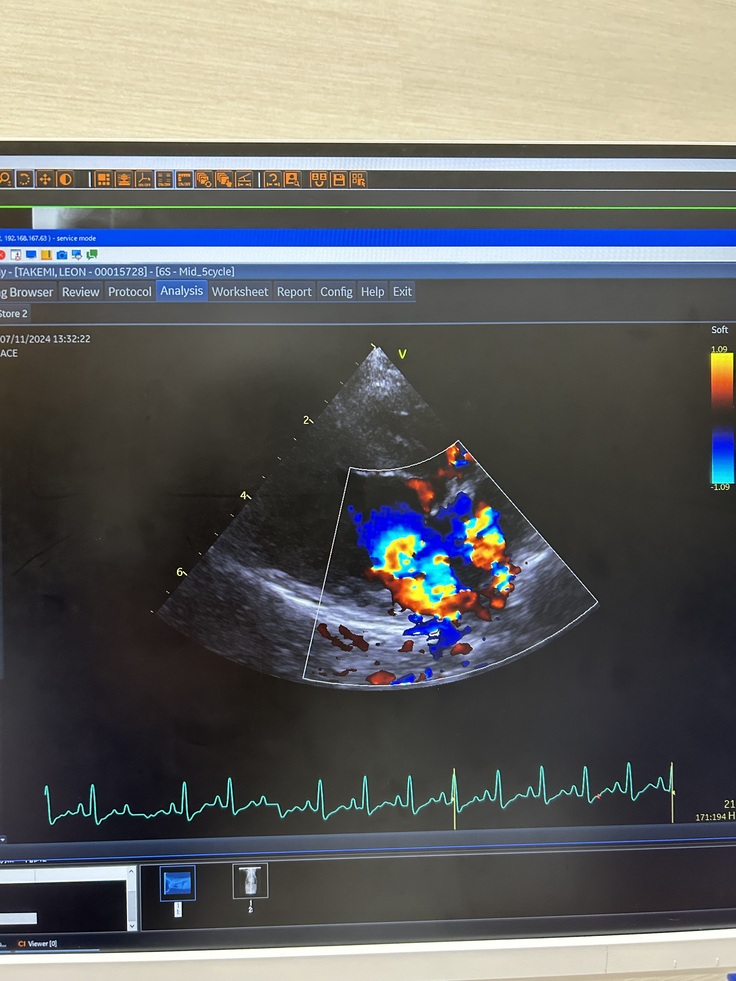

●エコー写真

写真のカラー部分が逆流した血液になります。

弁が何回か切れ、ボロボロの状態でした。